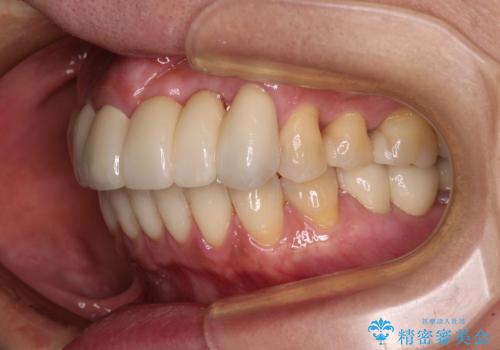

気になっている部分を全て治療したことで、費用はかかりましたが、仕上がりには大変満足していただき、治療をおこなって良かったと仰っていただきました。